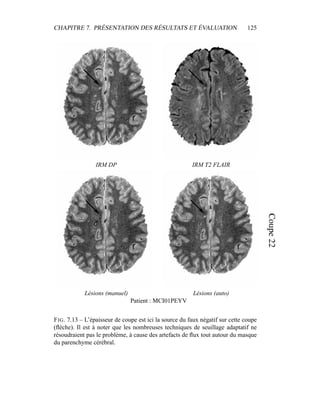

• 160.

CHAPITRE 8. DISCUSSIONET PERSPECTIVES 151 0.5 1 1.5 2 2.5 0 200 400 600 800 1000 1200 600 700 800 900 1000 1100 1200 IRMDP IRM T2 Matière blanche Matière grise LCR Interface matière grise / LCR 0.5 1 1.5 2 2.5 0 200 400 600 800 1000 1200 600 700 800 900 1000 1100 1200 IRMDP IRM T2 Matière blanche Matière grise LCR Interface matière grise / LCR FIG. 8.4 – Histogrammes conjoints des IRM T2 / DP, et visualisation des para- mètres de classes par les ellipses de Mahalanobis pour la matière blanche (blanc), la matière grise (gris), l’interface matière grise / LCR (pointillés) et le LCR (noir). L’histogramme du haut visualise le résultat avant correction du biais, en bas, après correction de biais. C’est ici un biais tissulaire entre le LCR cortical et le LCR ven- triculaire qui a été corrigé, ce qui explique une diminution de la variance de cette classe.

• 161.

CHAPITRE 8. DISCUSSIONET PERSPECTIVES 152 8.2 Analyse par type de lésion Les lésions de SEP ont une signature très variable, tant en termes de localisa- tion que de contraste ou de taille. Pour pouvoir mieux cibler les succès et échecs de la chaîne de traitements, les catégories de lésions – périventriculaires, juxta- corticales, corticales, lésions de la fosse postérieure, et les lésions nécrotiques – doivent être regardées séparément. 8.2.1 Lésions périventriculaires : contourage et faux positifs Les lésions périventriculaires sont les plus caractéristiques de la SEP et les plus nombreuses. Un bon traitement de ces lésions est donc un gage de bon fonction- nement pour un système d’analyse automatique d’IRM pour la SEP. Le choix de l’IRM T2 FLAIR pour la détection facilite grandement le travail : cette séquence assure en effet un très bon contraste entre le LCR, sombre, et les lésions qui ap- paraissent comme des hypersignaux forts : cette information est notre critère de détection. Par contre, essentiellement à cause des artefacts de flux, des hypersi- gnaux supplémentaires apparaissent et altèrent la qualité de la segmentation. – Des faux positifs sont ajoutés, par exemple entre les deux ventricules, mais aussi en général à l’interface parenchyme/LCR, comme par exemple autour des sillons corticaux (figure 8.5). – Les hypersignaux de la substance blanche en T2 FLAIR sont généralement une sur-segmentation des lésions périventriculaires de SEP (figure 8.5). La méthode choisie permet, la plupart du temps, d’écarter les faux positifs et de corriger le contourage, mais seulement d’une manière approximative. Nous allons voir pourquoi dans les paragraphes suivants, et prendrons deux exemples plus précis : le traitement des cornes ventriculaires et des artefacts de flux au niveau du plan médian sagittal, entre les deux ventricules. La solution choisie est de tracer la frontière entre le LCR et le parenchyme cé- rébral : tout hypersignal suspect à un distance inférieure à 2 mm de cette frontière est un artefact de flux ou un volume partiel, et doit donc être considéré comme